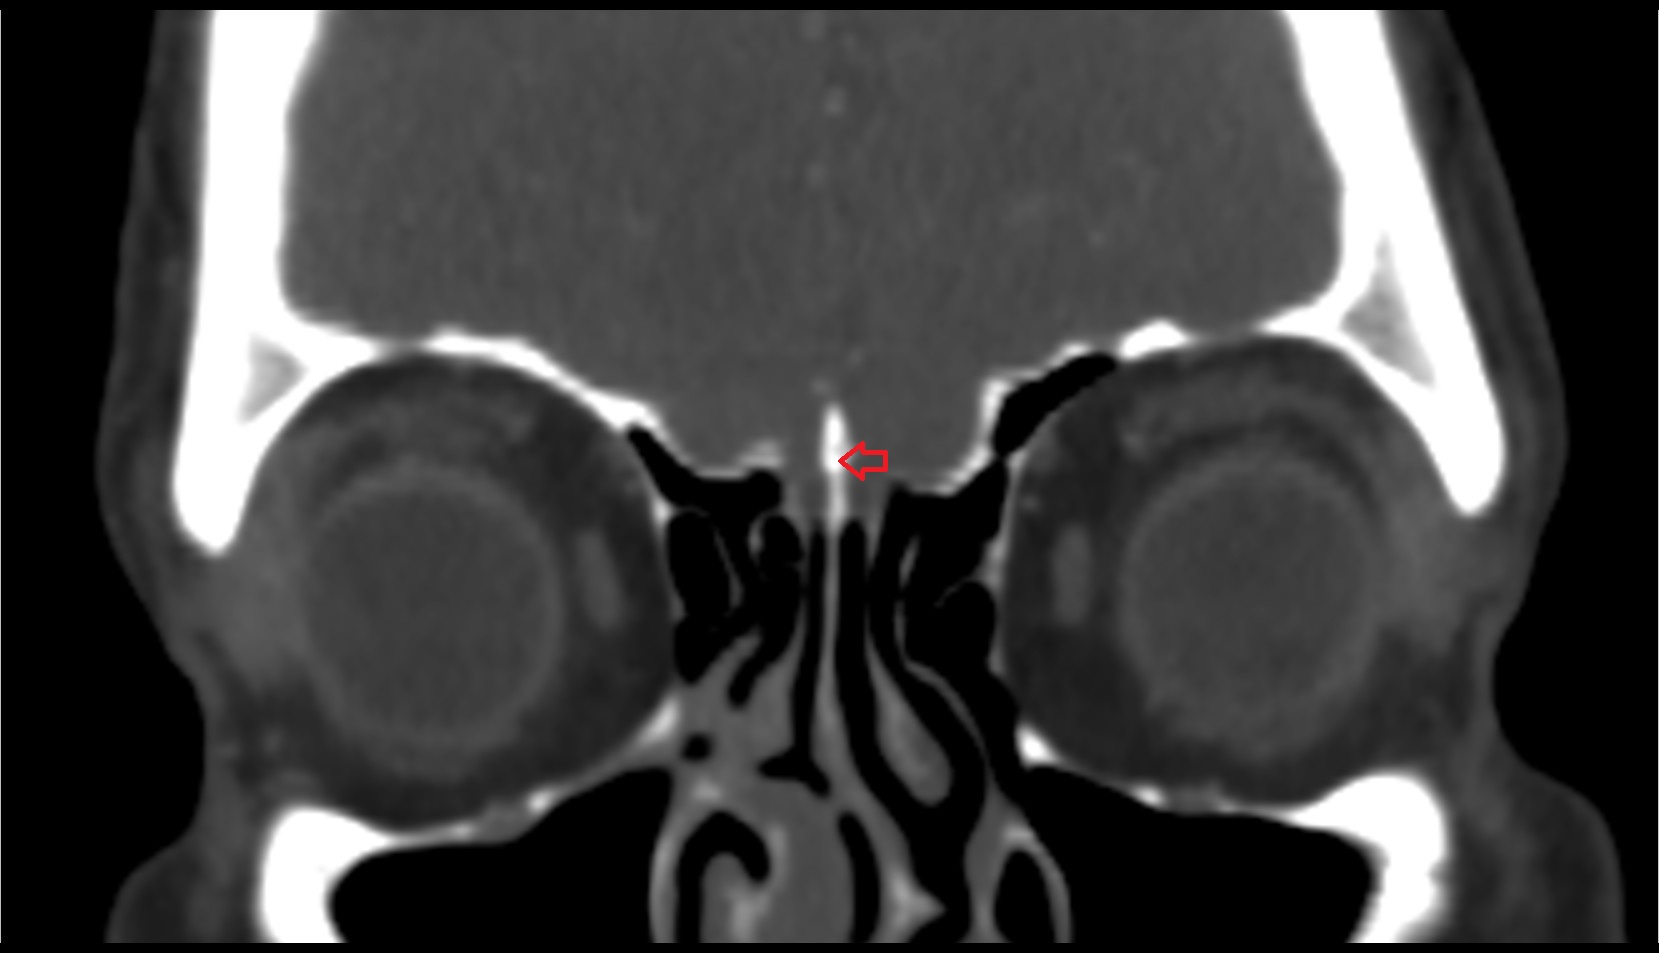

- Optic chiasm

- Optic canal

- Intracanalicular part of optic nerve

- Inferior orbital fissure

- Nasal septum

- Orbital plate